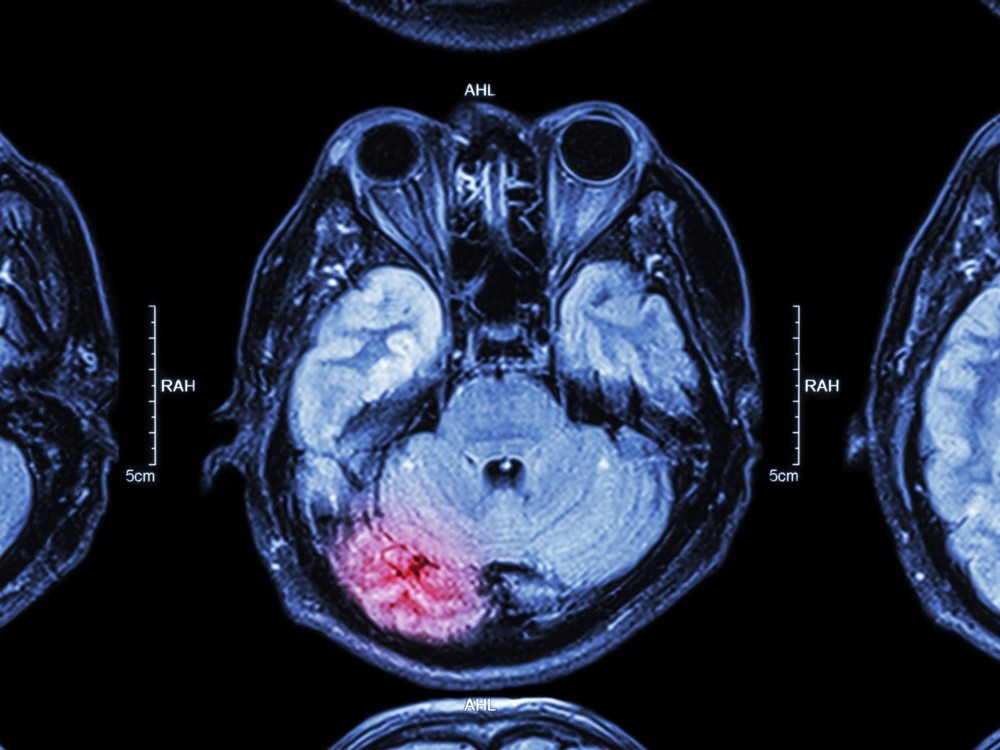

El estrés y las muchas afecciones como el consumo de alcohol, día tras día pueden ocasionar que el cerebro con el paso del tiempo corra riesgo de sufrir alguna lesión. Y cabe la posibilidad de que se presente y sea un ictus, en el siguiente articulo explicaremos de que trata además de mucha información importante y de que debes hacer para prevenirlo.